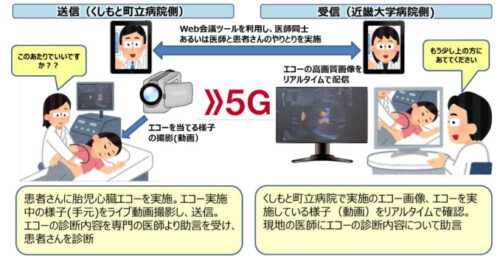

5G 通信を活用し 4K 映像伝送システム「LiveU」から胎児心臓エコー映像をリアルタイム伝送する実証実験を実施

5G を活用した遠隔医療支援を目的とし、胎児心臓エコー映像を 4K 映像伝送システム「LiveU(ライヴユー)」を用いて...